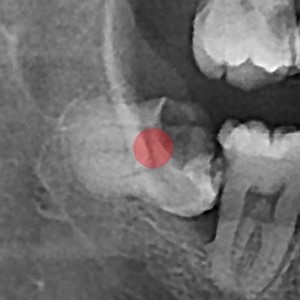

사랑니발치 30대/여성

5e20e086184bc11a2d853605b7813944_1764319778_1786.jpg